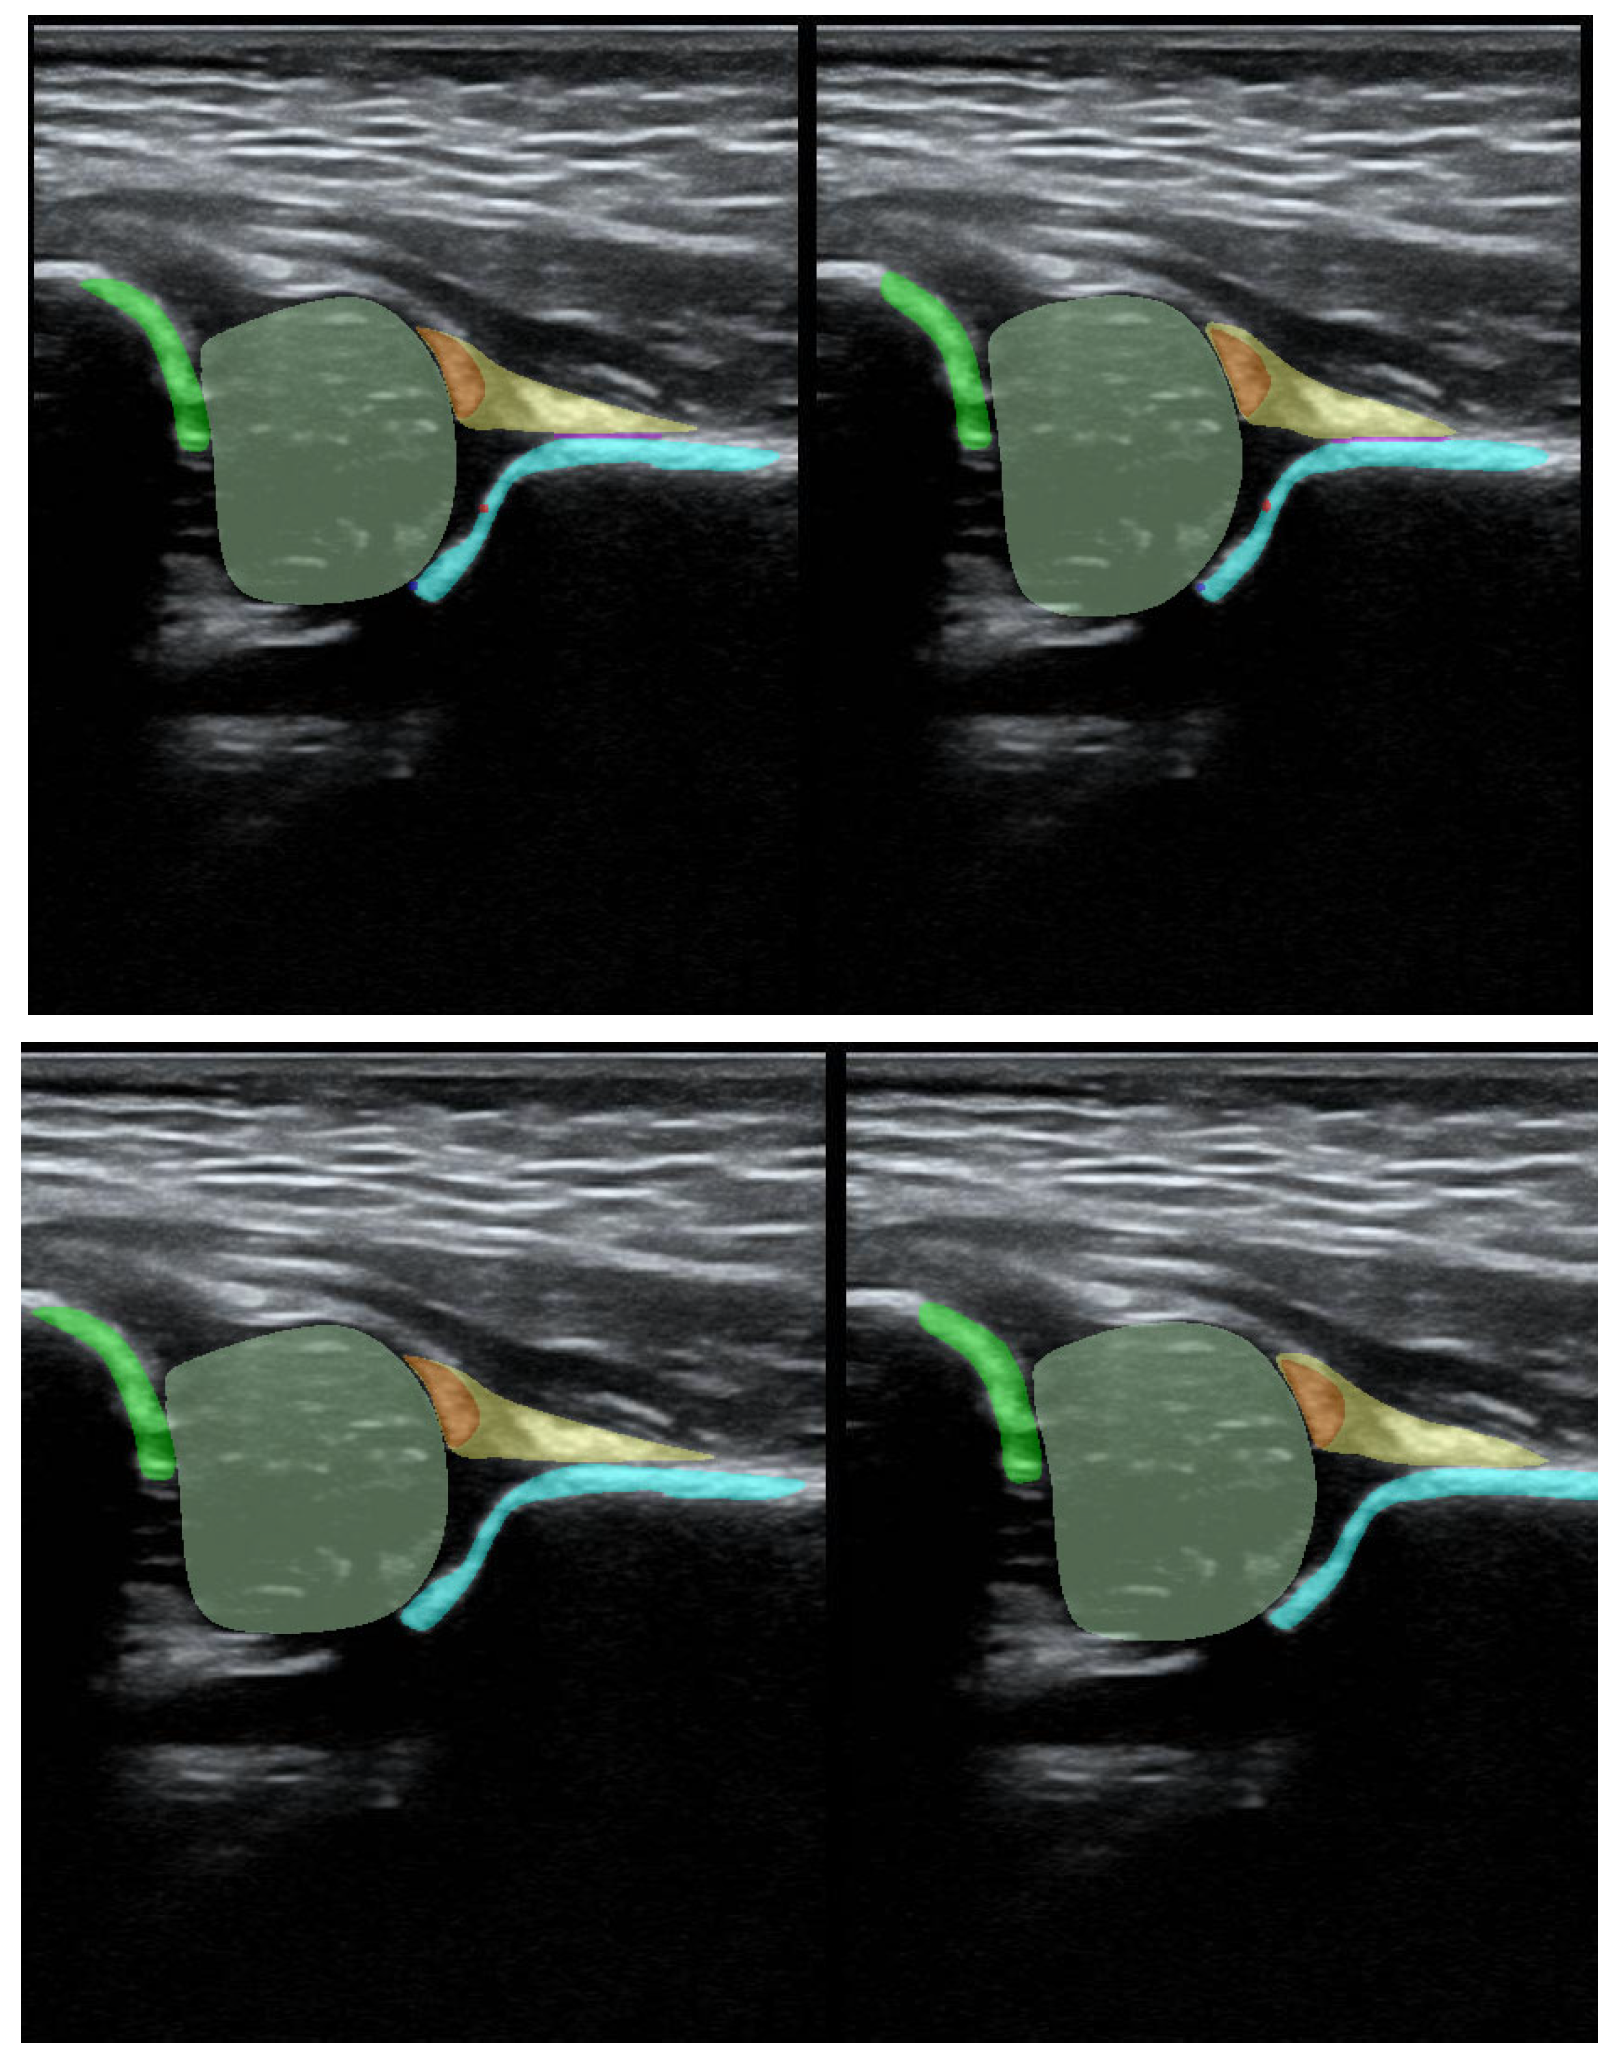

Figure 2. Result of pre-processing: extracting the USG area from the image and preparing masks for Model-5 (lower picture) and Model-8 (upper picture).

Additionally, during the model training process, the PaddleSeg library uses various pre-processing techniques (e.g., Resize, Normalize) and augmentation techniques (e.g., RandomHorizontalFlip, RandomDistort), which were also used in our training. The first step of pre-processing involved cropping the images to the ultrasound area to eliminate regions that do not pertain directly to the ultrasound scan. The second step involved the preparation of masks containing only 5 classes (chondro-osseous border, femoral head, labrum, cartilaginous roof, and bony roof). This step was performed to create the input for Model-5 (Figure 2).